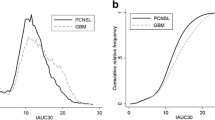

Single and multiple-parameter diagnostic performance

The single-parameter diagnostic performance results used to differentiate PCNSL and GBM are summarized in Table 3. The single-parameter diagnostic performance results used to differentiate atypical PCNSL and GBM are summarized in Table 4. The AUC of the rADCmean was higher than rADCmax and rADCdif. The parameters rADCmean, CBFmax, and nET volume ratio had the highest AUC value and were selected for assessment as a multiparameter. The multiparametric diagnostic performance results used to differentiate between atypical PCNSL and GBM are summarized in Table 5. The AUC of paired imaging parameters (rADCmean and CBFmax, rADCmean and nET volume ratio, and CBFmax and nET volume ratio) was higher than that for any single parameter, and the three-variable combination (rADCmean, CBFmax, and nET volume ratio) was superior to the two-variable combination. The AUC of the three-variable model (rADCmean, CBFmax, and nET volume ratio) was 0.96, the sensitivity was 90%, and the specificity was 96.55%, which was superior to that of the two-variable model, as shown in Fig. 6.

Receiver operating characteristic curves combining two and three parameters were compared to distinguish between atypical PCNSL and GBM. PCNSL, primary CNS lymphoma; GBM, glioblastoma; rADCmean, relative mean apparent diffusion coefficient; CBFmax, maximum cerebral blood flow; nET, non-enhancing tumor